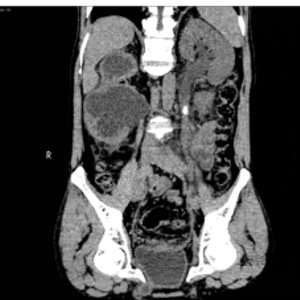

入院后,三维CT发现患者双侧输尿管结石,右肾盂输尿管连接处狭窄,右肾严重积水,左肾也因结石梗阻导致肾盂输尿管积水。肌酐1284.5μmoI/L,已经达到急性肾功能不全(尿毒症期)。王春阳教授立即为患者进行超声引导下右肾穿刺造瘘,改善患者肾功能,并制定拟行达芬奇手术机器人辅助腹腔镜下双侧输尿管切开取石术+达芬奇手术机器人辅助腹腔镜下右侧肾盂成型肾盂输尿管再吻合术,决定一次手术解决目前导致患者肾脏积水的全部问题。

王春阳教授介绍,仅利用一次手术同时处理患者全部问题,大大增加手术难度,但能减轻患者的痛苦和费用。对于结石大、梗阻明显、结石坎顿的病人,为及时解决梗阻,挽救肾功能,可选择输尿管切开取石。传统的输尿管切开取石手术疗效可靠,但患者手术创伤大,恢复慢,住院时间长。运用达芬奇手术机器人辅助腹腔镜下行输尿管切开取石术不切断肌肉,不损伤较大血管神经,手术直视下进行,术野可放大10倍,手术损伤小,出血少,恢复快。同时该病人CT中表现出右侧肾盂输尿管连接部狭窄,切开取石后行右侧肾盂成形术,去除狭窄段,对肾盂输尿管连接部重新塑形,显著解除梗阻。